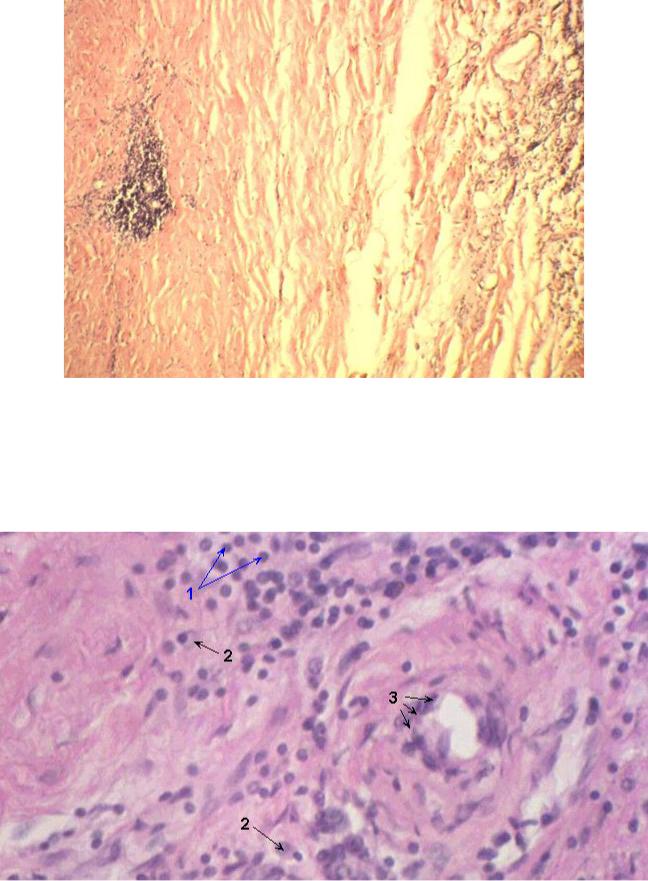

Микропрепараты: Лимфогранулематоз и Нодулярный Склероз